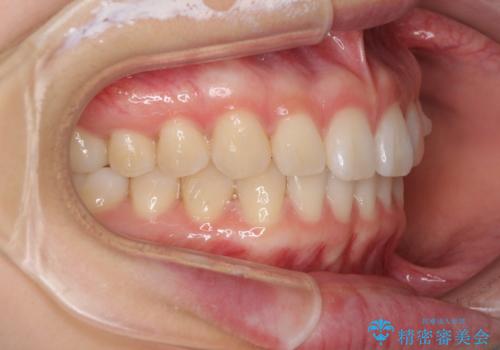

インビザラインによるすきっ歯の改善

- 上の前歯の隙間を気にして来院された患者様です。

インビザラインにより、隙間を閉じながら、隙間の原因であるディープバイトを改善していくこととしました。